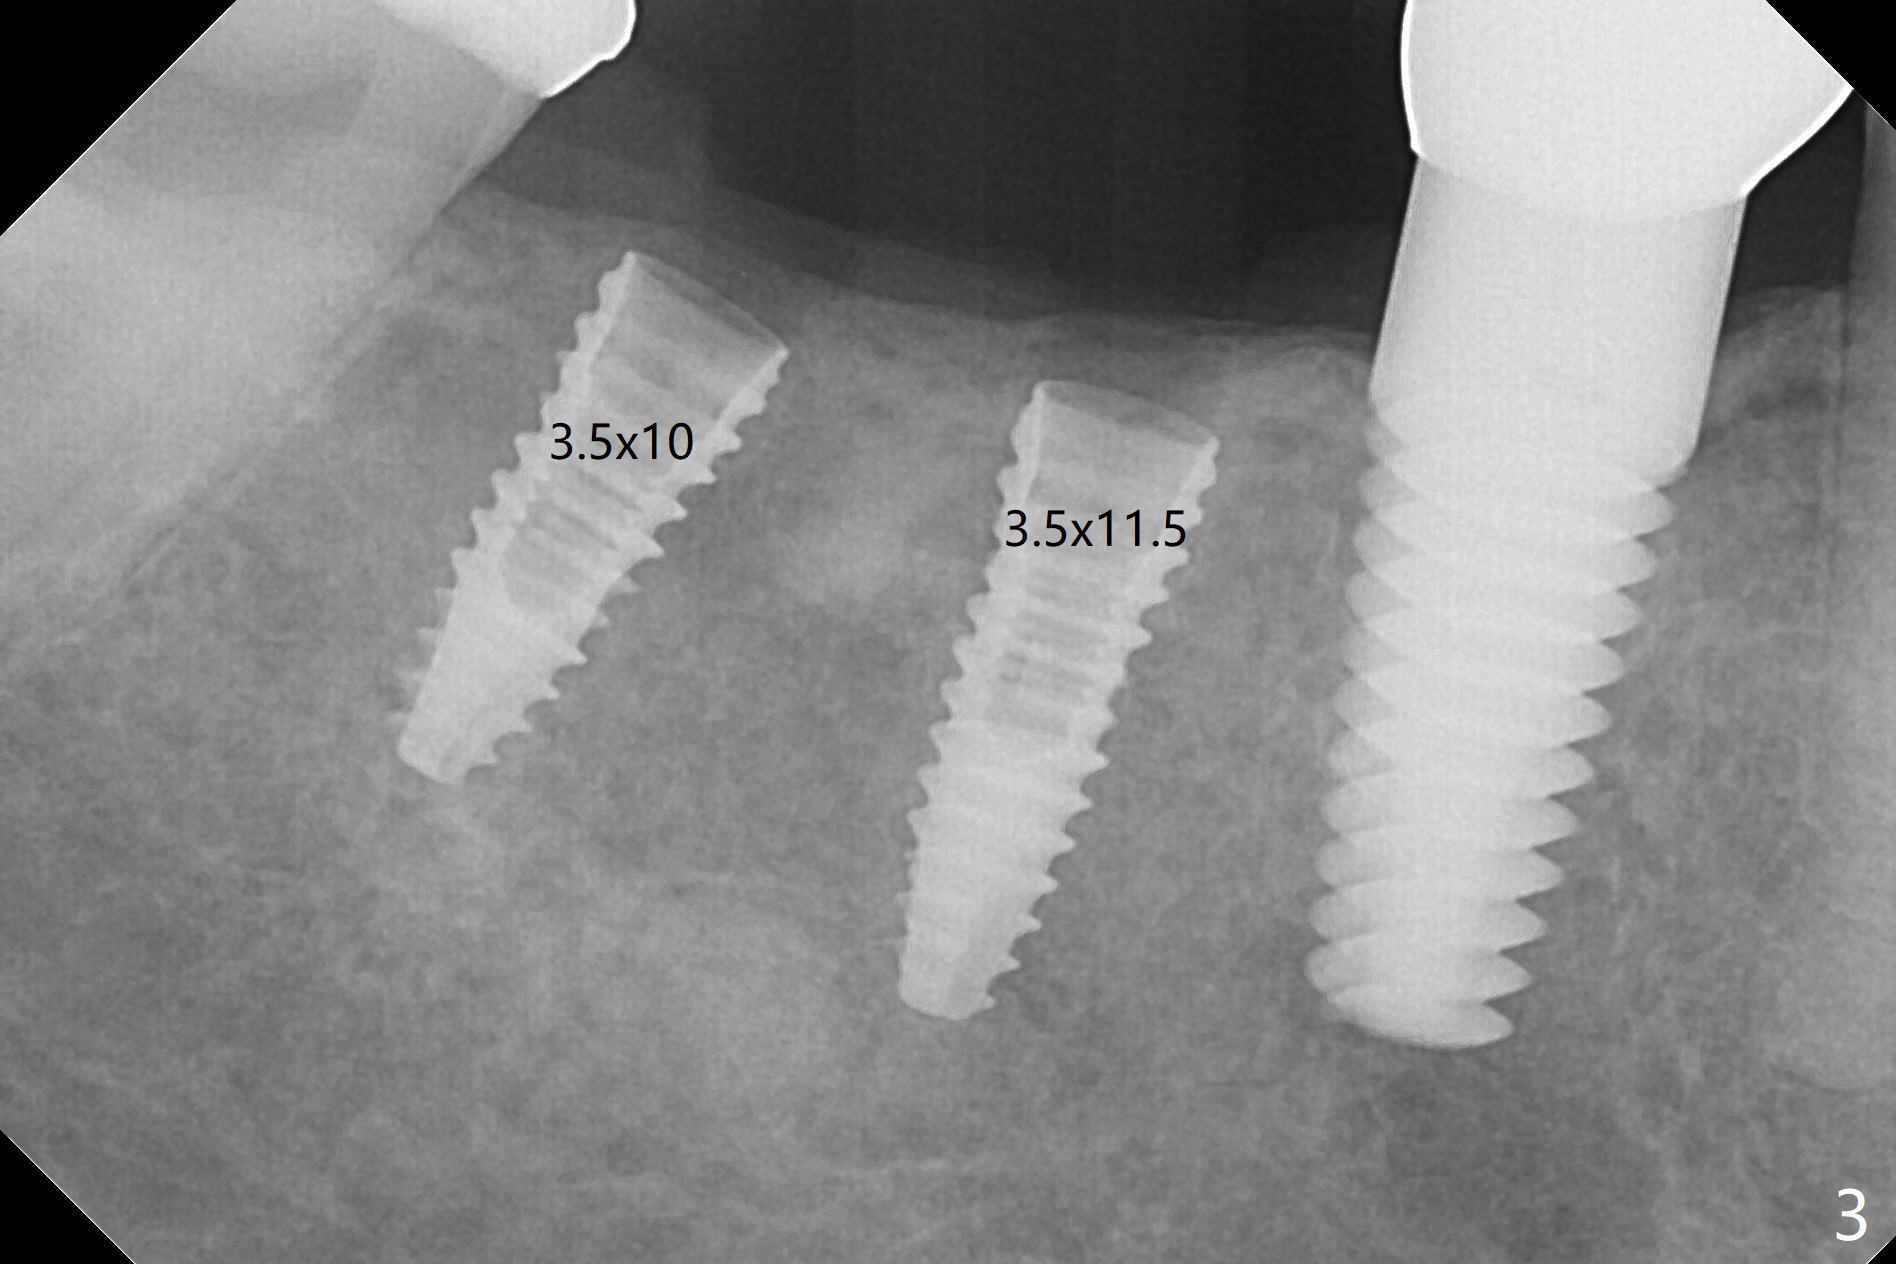

To reduce patient's expense, two implants are to be placed in narrow mesiodistal space (#30 and 31) free hand. Time is spent to determine where to place 4 mm tissue punch. When initial osteotomy is established (Fig.1), effort is paid to deciding whether the osteotomy is close to the Inferior Alveolar Canal (Fig.2 red dashed line). Since the gingiva is thin (Fig.4), implants switch to bone level ones (Fig.3,4). To have enough space between implants and the neighboring tooth, two of 3.5 mm implants are placed. Because of the limited vertical restoration height, the implants are chosen intraoperatively to be short and placed deep (Fig.3). Guided surgery planning can solve these pieces of dilemma beforehand.

In fact, detailed measurements after parallel pins indicate that the osteotomy at #30 should be moved distal (Fig.5 arrow), which is consistent with post placement measurements (Fig.6).